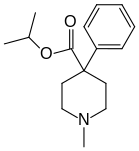

4-Phenylpiperidines

Pethidines (meperidines)

Structures